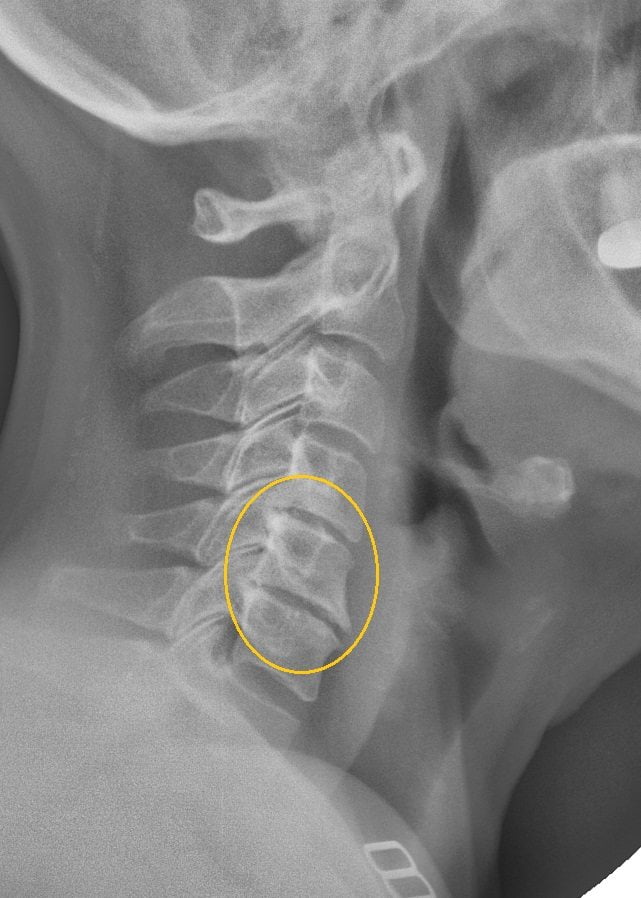

- рентгенография позвоночного столба и легких;

- КТ или МРТ;

Если терапевт, а именно к нему часто обращаются пациенты с кашлем, не обнаружил признаков инфицирования и присутствия посторонних предметов, то он проводит дальнейшее обследование больного. Обычно в таких случаях причиной становится или прием определенных препаратов для снижения артериального давления (Эналаприл, Лизиноприл), или остеохондроз. Диагностировать последний позволяет изучение рентгенографических изображений.

На них хорошо визуализированы истончившиеся межпозвонковые диски, сместившиеся позвонки, разросшиеся края костных пластинок. Пациент направляется для дальнейшего лечения к вертебрологу или неврологу.